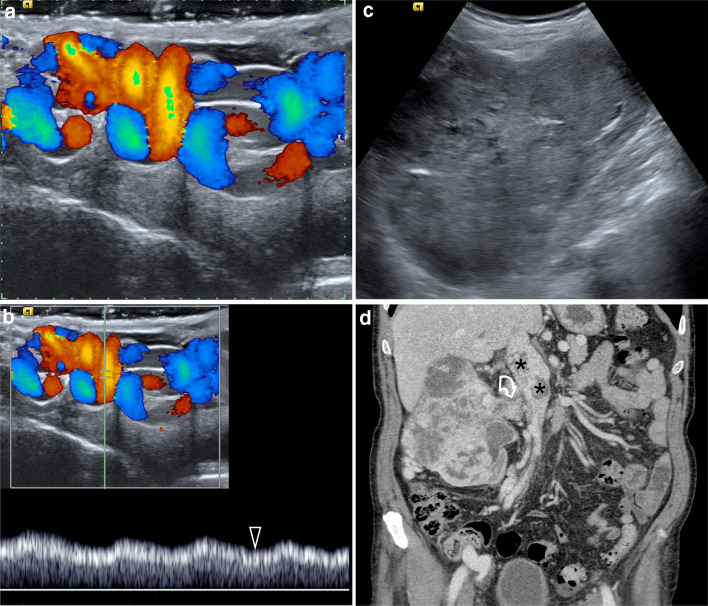

In conclusion, suspicion of a secondary varicocele can arise when a clinically evident varicocele presents acutely, and remains tense in a supine position. Secondary subclinical varicocele has not been reported. The ESUR-SPIWG believes that US examination should always be extended to the abdomen in children less than 9 years presenting with an acute varicocele, to rule-out a renal or retroperitoneal tumour. In adults, the alleged association between varicoceles and retroperitoneal masses is based on a limited number of series and case reports in which the varicocele was a late sign of a symptomatic, palpable lesion [152, 166–169].

Although the possibility of missing an undetected retroperitoneal lesion during a Doppler investigation for varicocele when the abdomen is not evaluated in an adult is very unlikely, it cannot be completely excluded (Fig. 7). Patients often undergo US examinations without a full clinical evaluation, and even obvious abdominal findings can be missed. As a consequence, the ESUR-SPIWG believes that the sonologist is fully justified in extending the US examination to the abdomen when the varicocele is of acute onset, whatever the side (left or right), and particularly when it remains unchanged in the supine position. Otherwise, the US practitioner should refer the patient to an internal medicine specialist for a complete diagnostic evaluation including an abdominal examination (Table 2, recommendation 21–22).

Fig.7.

Secondary varicocele in an 85-year-old patient presenting with a right scrotal lump. a Colour Doppler ultrasound of the right spermatic cord shows markedly dilated pampiniform plexus with basal reflux. b Spectral Doppler interrogation obtained in an upright position shows no changes during Valsalva’s maneuver (arrowhead). c Ultrasound interrogation of the right kidney shows a large renal tumour. d Contrast-CT scanning showing a large right renal tumour growing into the right renal vein (curved arrow) and inferior vena cava (asterisks)